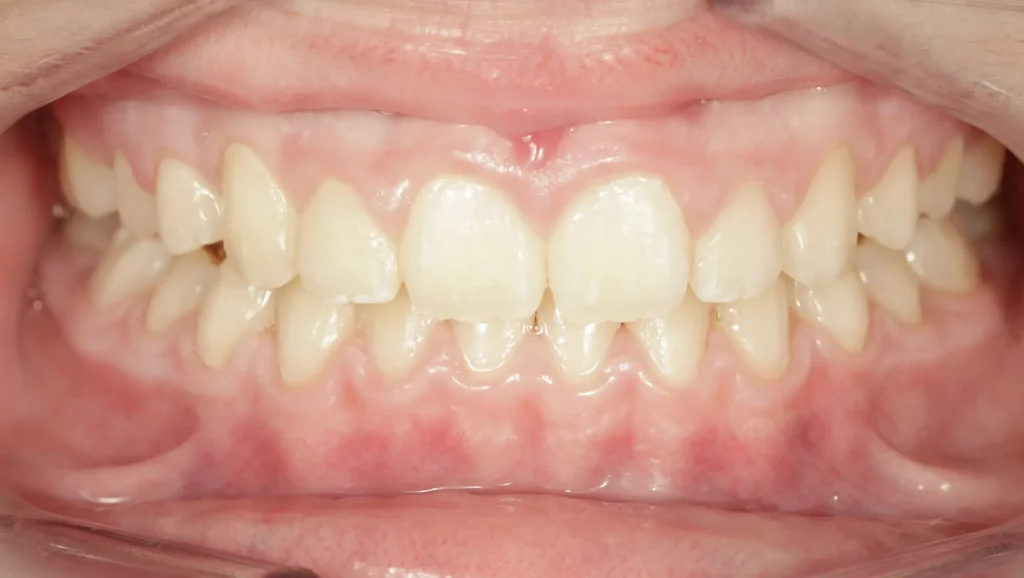

En este caso, la paciente presentaba una maloclusión clase II, caracterizada por un desajuste entre los maxilares superior e inferior. Específicamente, se observaba una mordida cruzada, donde los dientes superiores no se alineaban correctamente con los dientes inferiores. Además, la paciente tenía apiñamiento dental en la zona anterior del maxilar superior.

Al inicio del tratamiento, la paciente presentaba un mal posicionamiento de los dientes, lo que generaba tanto una sonrisa desalineada como una función masticatoria comprometida. La mordida cruzada era evidente en la parte frontal, donde los dientes superiores se desplazaban hacia adentro, en lugar de encajar adecuadamente con los dientes inferiores. Además, el apiñamiento de los dientes superiores también dificultaba el alineamiento correcto.